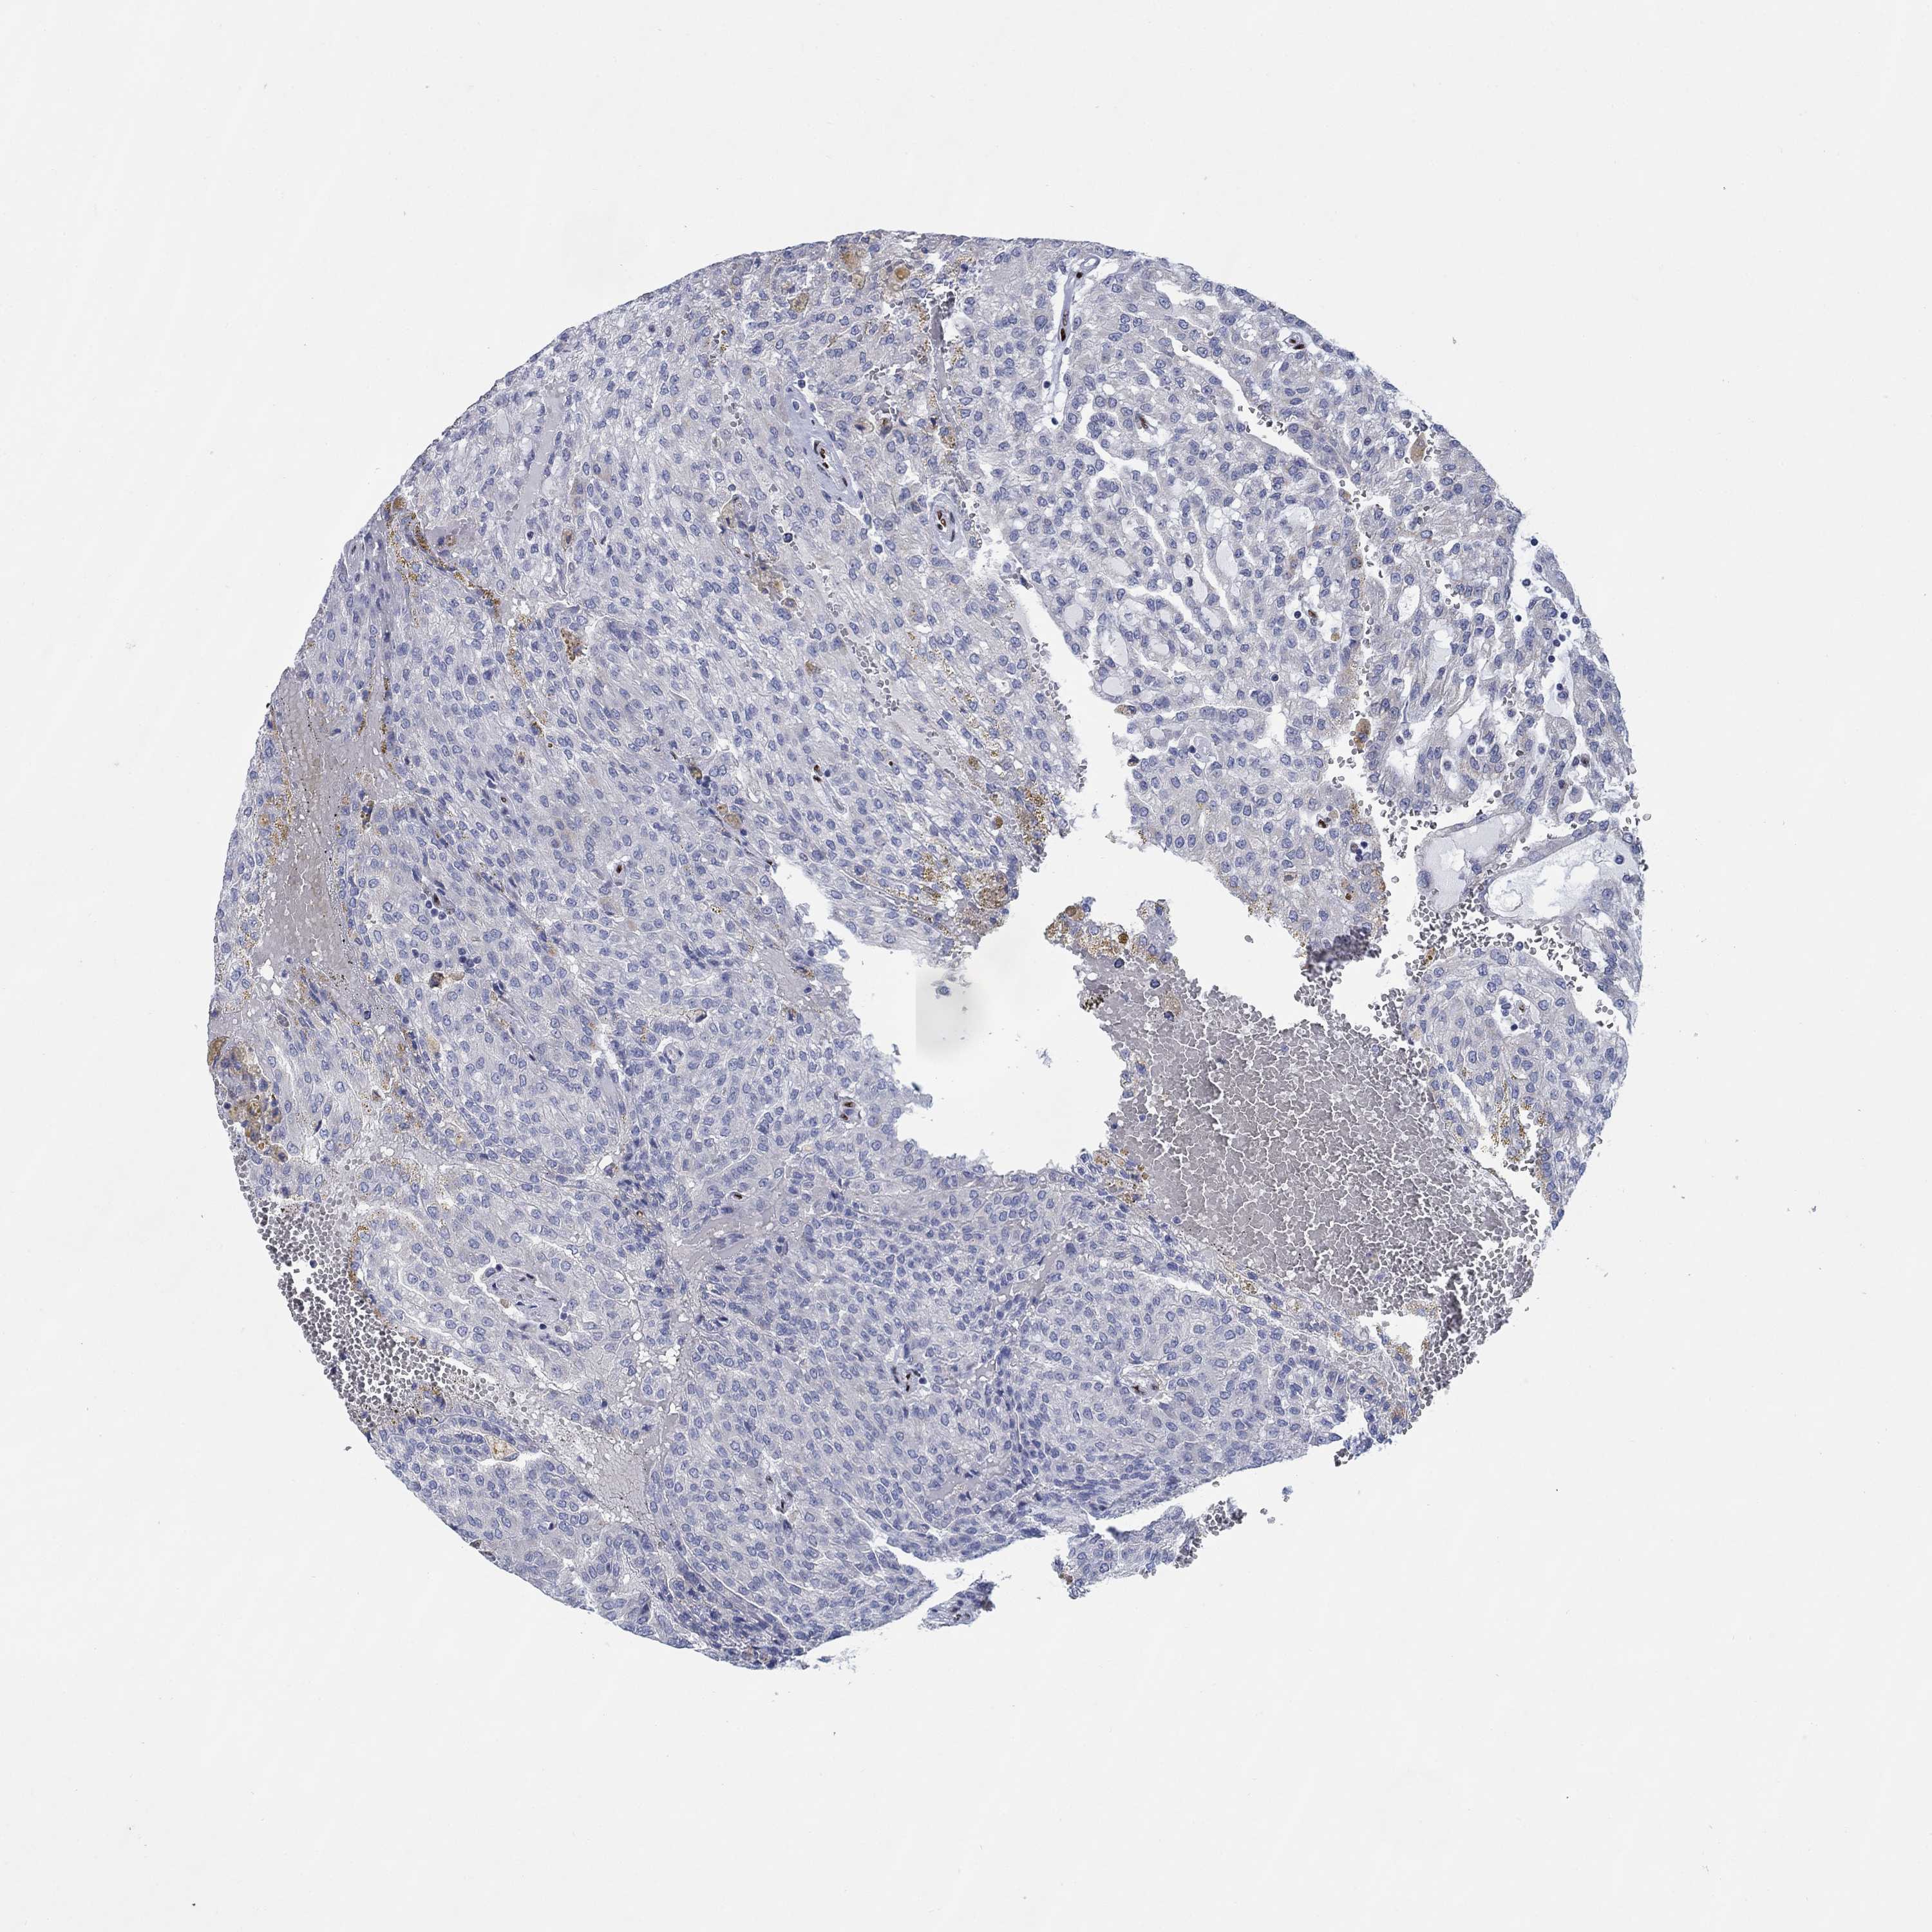

KIDNEY RENAL CLEAR CELL CARCINOMA (TCGA) - Interactive survival scatter ploti

The Survival Scatter plot shows the clinical status (i.e. dead or alive) for all individuals in the patient cohort, based on the same data that underlies the corresponding Kaplan-Meier plots. Patients that are alive at last time for follow-up are shown in blue and patients who have died during the study are shown in red.

The x-axis shows the expression levels (FPKM) of the investigated gene in the tumor tissue at the time of diagnosis. The y-axis shows the follow-up time after diagnosis (years). Both axes are complimented with kernel density curves demonstrating the data density over the axes. The top density plot shows the expression levels (FPKM) distribution among dead (red) and alive patients (blue). The right density plot shows the data density of the survived years of dead patients with high and low expression levels respectively, stratified using the cutoff indicated by the vertical dashed line through the Survival Scatter plot. This cutoff is automatically defined based on the FPKM cutoff that minimizes the p-score. The cutoff can be changed by dragging the vertical line or by entering a cutoff value in the square labeled "Current cut-off".

Under the Survival Scatter plot the p-score landscape (black curve; left axis) is shown together with dead median separation (red curve; right axis). Dead median separation is the difference in median mRNA expression between patients who have died with high and low expression, respectively. It is calculated as follows: median FPKM expression of dead patients with high expression - median FPKM expression of dead patients with low expression. This is intended to aid the user in visually exploring custom cutoffs and the associated p-scores and dead median separation.

Individual patient data is displayed and can be filtered by clicking on one or more of the category buttons on the top of the page. Categories describing expression level and patient information include: high, low, alive, dead, female, male and tumor stages. The scale of the x-axis can be toggled between linear and log-scale by clicking on the "x log" button. Mouse-over function shows TCGA ID, patient information and mRNA expression (FPKM) for each patient.

& Survival analysisi

Kaplan-Meier plots summarize results from analysis of correlation between mRNA expression level and patient survival. Patients were divided based on level of expression into one of the two groups "low" (under cut off) or "high" (over cut off). X-axis shows time for survival (years) and y-axis shows the probability of survival, where 1.0 corresponds to 100 percent.

ZEB1 is validated prognostic, high expression is favorable in Kidney Renal Clear Cell Carcinoma (TCGA)

Best expression cut offi

Based on the FPKM value of each gene, patients were classified into two groups and association between prognosis (survival) and gene expression (FPKM) was examined. The best expression cut-off refers the FPKM value that yields maximal difference with regard to survival between the two groups at the lowest log-rank P-value. Best expression cut-off was selected based on survival analysis .

When clicking on this number, the vertical dashed line indicating cut-off, the interactive survival plot, and the Kaplan-Meier curve will be adjusted to show results based on the best expression cut-off.

: 14.71

Median expressioni

Median expression refers to the median FPKM value calculated based on the gene expression (FPKM) data from all patients in this dataset. When clicking on this number, the vertical dashed line indicating cut-off, the interactive survival plot, and the Kaplan-Meier curve will be adjusted to show results based on the median expression.

: N/A

Median follow up timei

Median follow up time refers to the median time (years) after diagnosis with this type of cancer, based on clinical data from all patients in this dataset.

P scorei

Log-rank P value for Kaplan-Meier plot showing results from analysis of correlation between mRNA expression level and patient survival.

N/A

5-year survival highi

5-year survival for patients with higher expression than the expression cutoff.

For melanoma and glioma, 3-year survival is shown.

5-year survival lowi

5-year survival for patients with lower expression than the expression cutoff.

TCGA RNA samplesi

RNA-seq data is reported as average FPKM (number Fragments Per Kilobase of exon per Million reads), generated by the The Cancer Genome Atlas (TCGA) .

Normal distribution across the dataset is visualized with box plots, shown as median and 25th and 75th percentiles. Points are displayed as outliers if they are above or below 1.5 times the interquartile range. FPKM values of the individual samples are presented next to the box plot.

Average pTPM 13.9

Number of samples 521